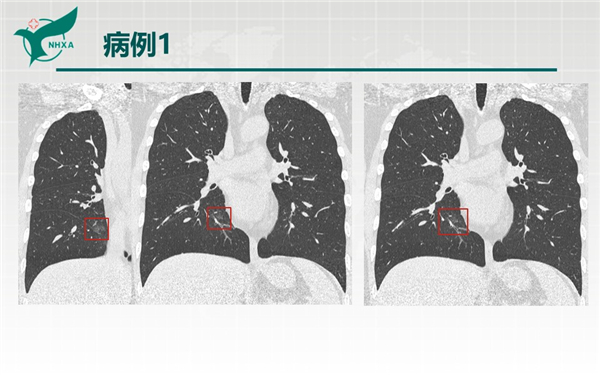

【病例分享】新型冠狀病毒肺炎3例(西安市第九醫(yī)院)